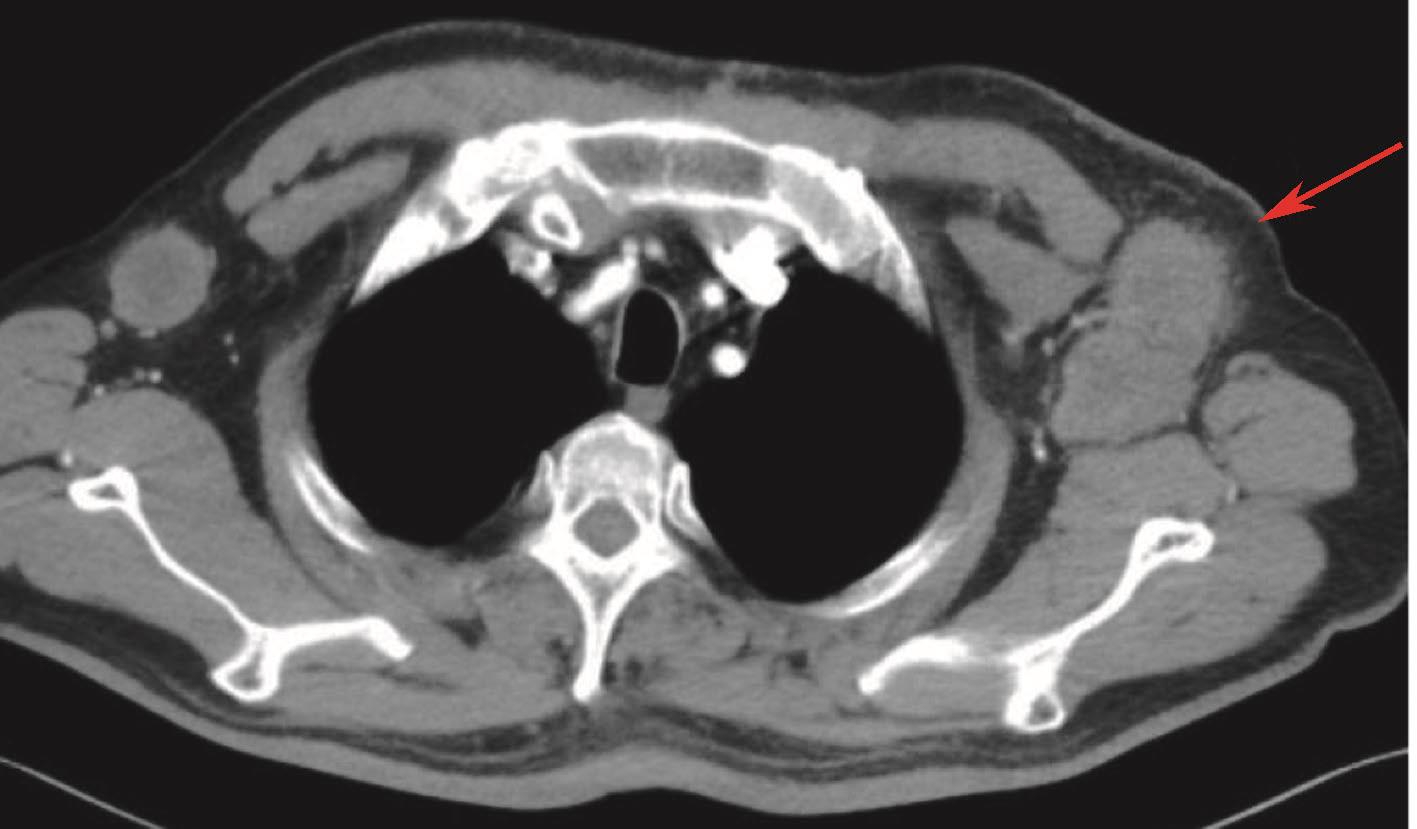

2017-11复查颈胸腹盆增强CT:新见左侧胸锁乳突肌下方、双侧腋窝多发淋巴结(图7)。考虑PD。

图7 胸腹盆增强CT:提示双侧腋窝多发淋巴结